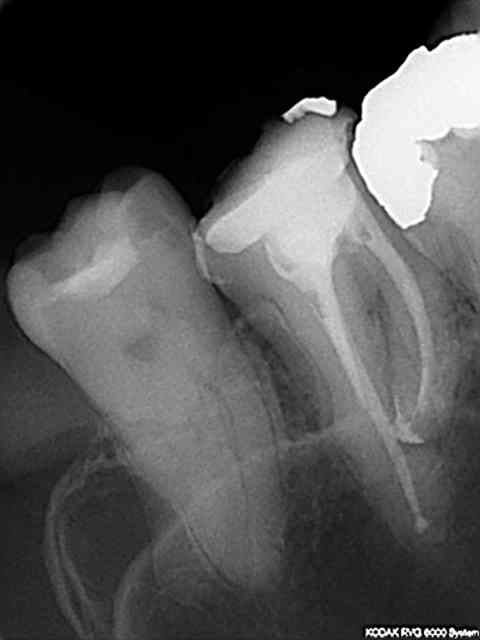

1 .Essayage cones en place, couper ce qui dépasse le cas échéant ( une sur instrumentation ca arrive)

2. scellement des cones.

3. couper les cones au friendo puis phase de descente au friendo ( qui est un heater plugger je le rappelle) et compactage au machtou.

4. coincer les chutes de gutta à l' entrée des canaux et les thermo-compacter au mac spadden.

C'est pret ! -))))